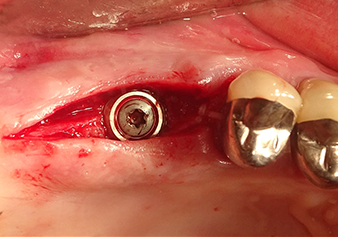

Implant bed preparation and augmentation

Following an intermediate check (Fig. 4) a further preparation step was performed (Fig. 5). Afterwards, the hydraulic Z35P instrument was used to lift the membrane to the desired position (Fig. 6 and 7). This was followed by further piezosurgical preparation of the implant bed, concluded with a rotary bur and shoulder milling cutter up to the implant diameter of 4.8 mm. Before the implant was inserted, the augmentation material (particle size approx. 0.8-1.6 mm) was introduced underneath the Schneiderian membrane (Fig. 8).